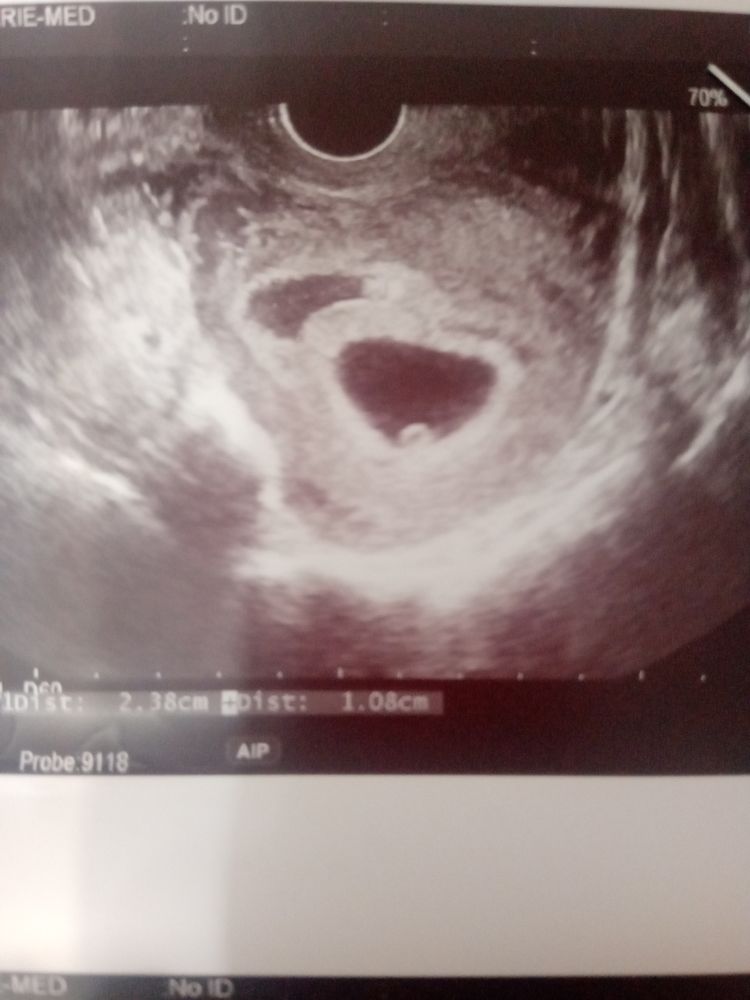

Здравствуйте, скажите а по узи можно ли определить где именно расположена гематома?

есть фото узи, но что-то не помню что бы мне на узи сказали где она расположена, слышала что от места расположение зависит серьезность гематомы

нп фото Узи она по цвету отличается

смотрите по контуру плодного яйца (высветление )

Вот гематома с четвертой дочей. Локация четко видна. Если гематома организованная, то это не страшно.